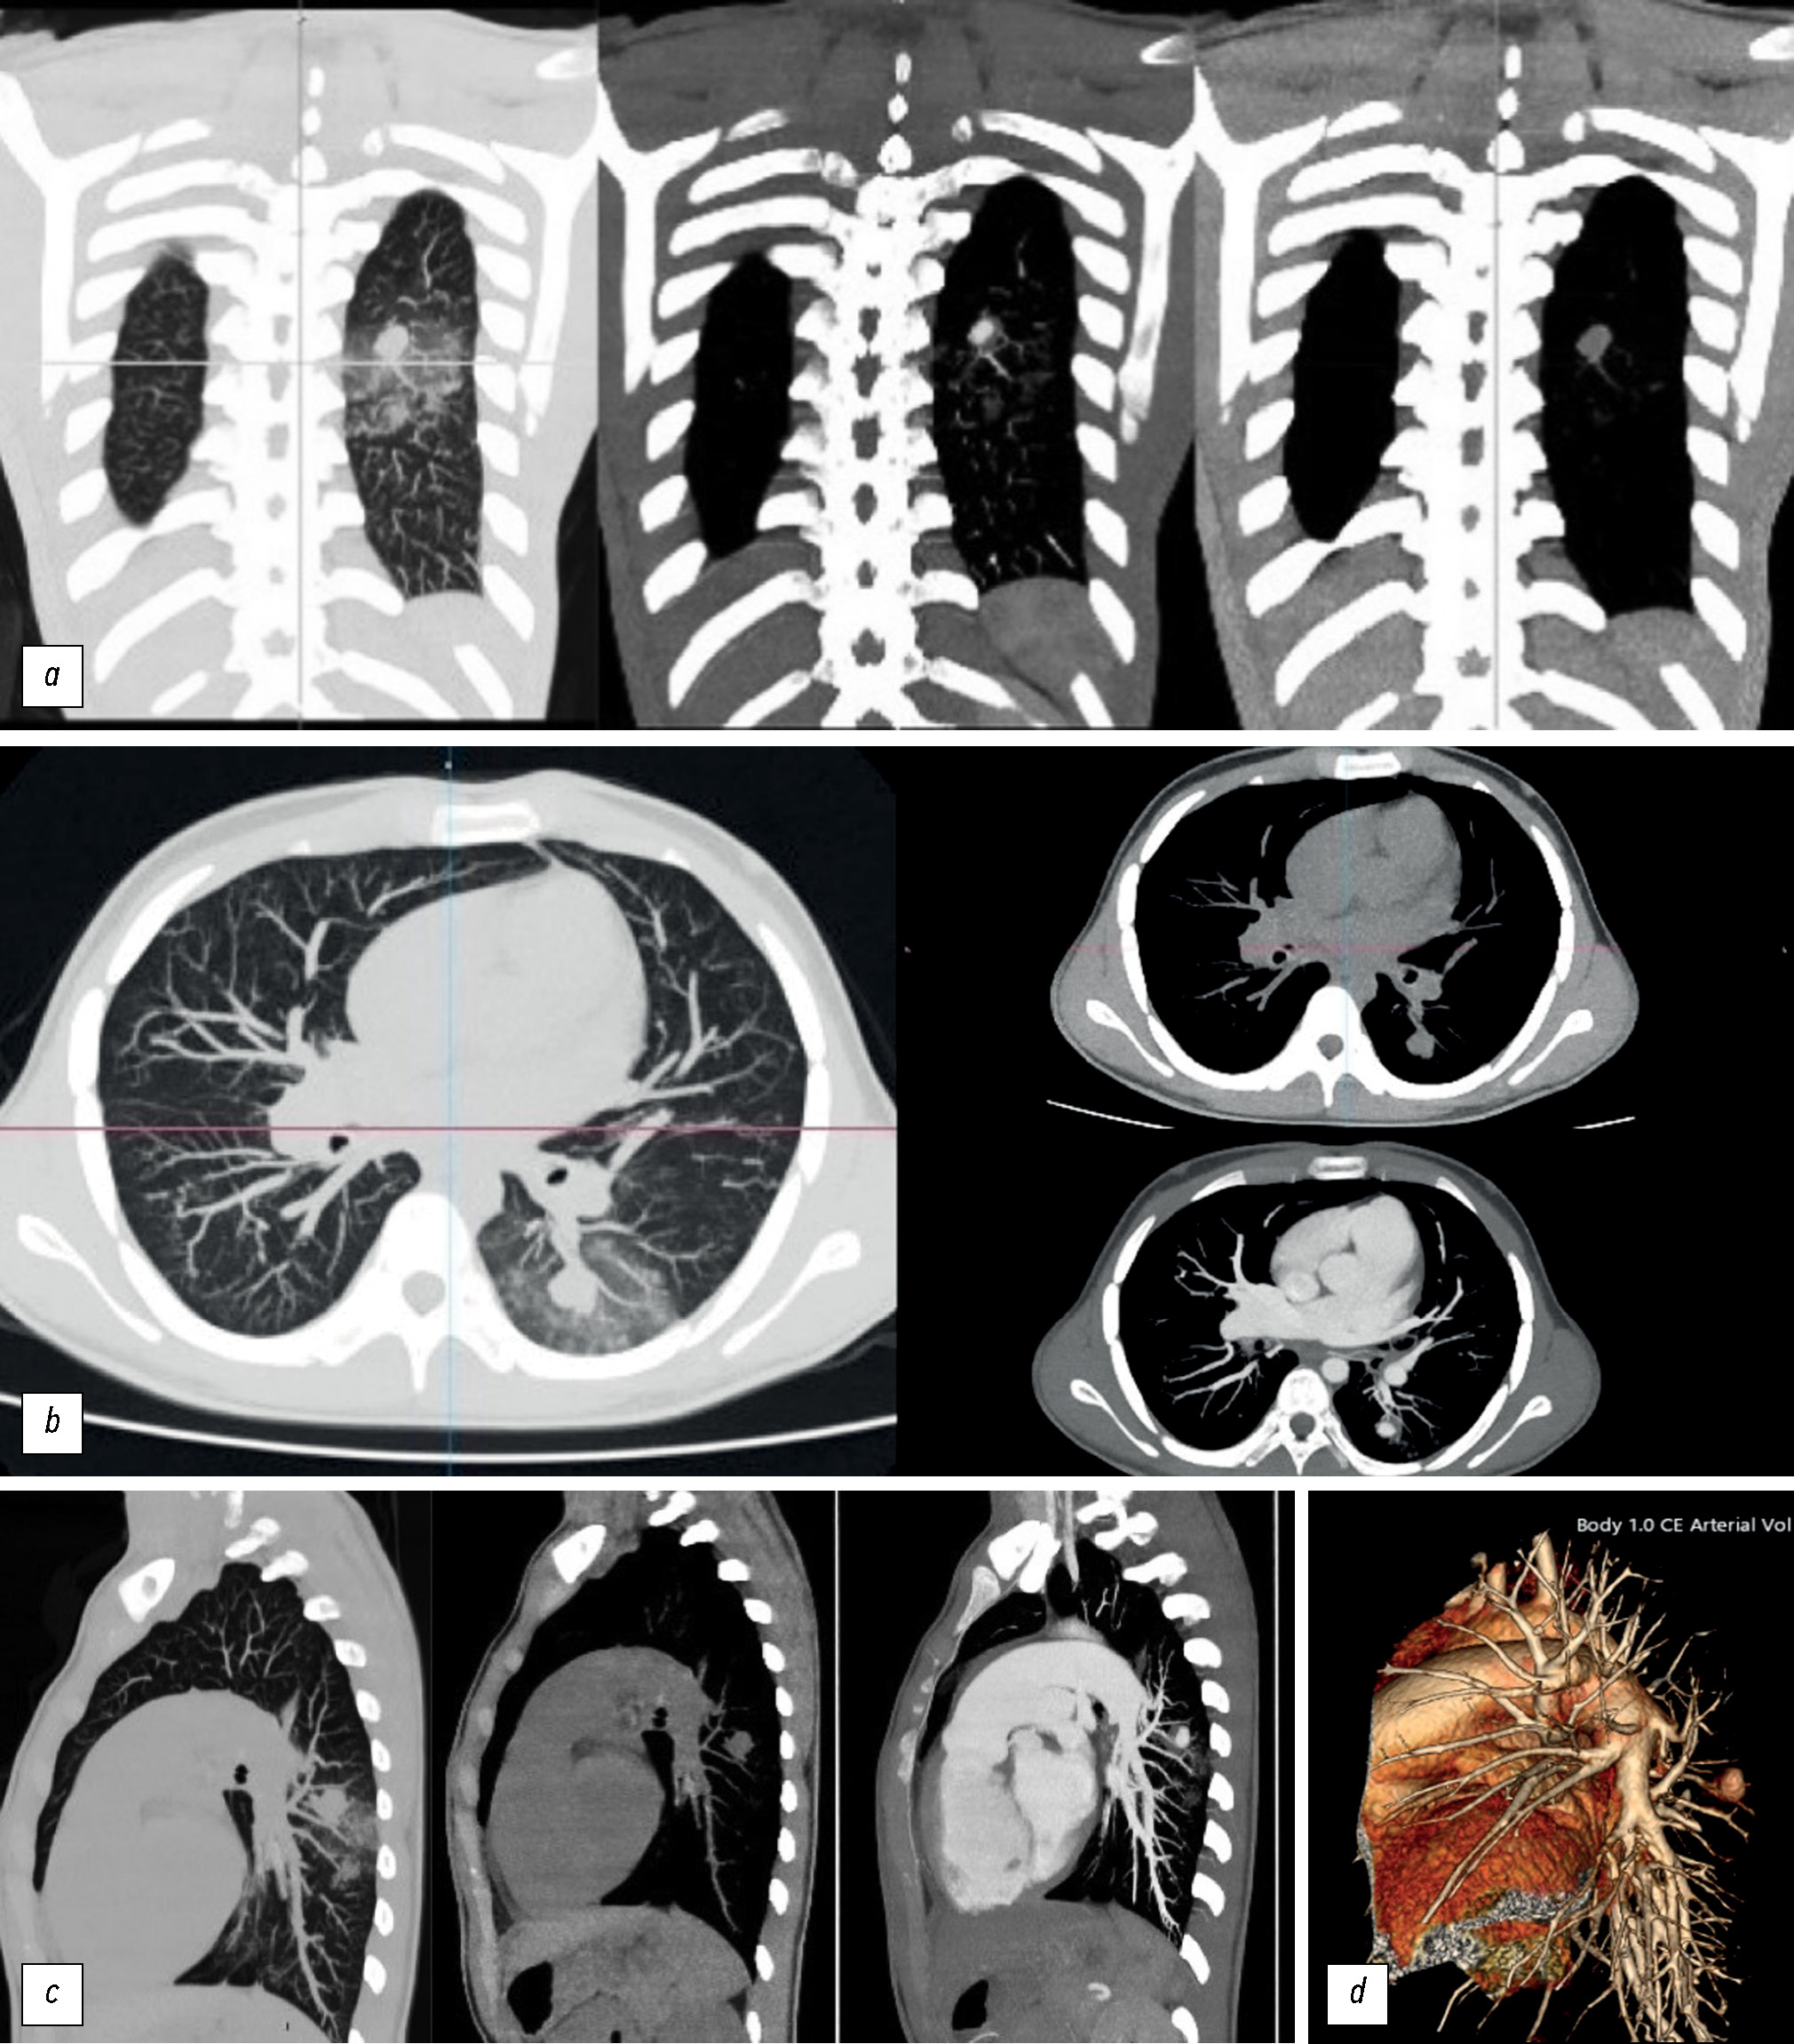

Результаты КТА указывали на массивное поражение и участки инфильтрации в VΙ сегменте левого лёгкого (рис. 2). Контрастное усиление узла совпадало с кровяным депо, что подтверждает сосудистое происхождение нарушения. Кроме того, были расширены правые отделы сердца и лёгочная артерия.

Рис. 2. Наблюдение в режиме лёгочного окна и мягких тканей поражение в VΙ сегменте левого лёгкого округло-овальной формы, размером 1,6×1,4×1,2 см, плотностью до 27 единиц Хаунсфилда на фоне инфильтративных изменений, свидетельствующее о внутрипаренхиматозном кровоизлиянии: a — снимок во фронтальной плоскости, b — снимок в аксиальной плоскости; c — снимок в сагиттальной плоскости; d — аневризма сегментарной ветви лёгочной артерии, показанная с помощью 3D-реконструкции.